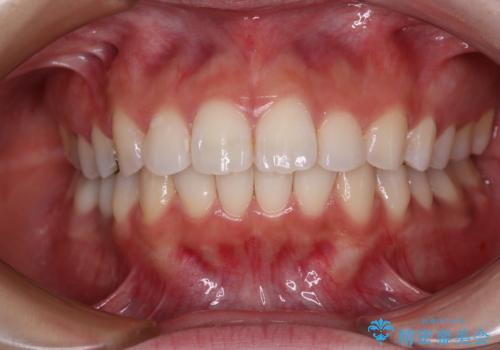

欠損した歯と前に飛び出した前歯 インプラント治療を併用したワイヤー矯正治療

上顎歯列全体を後方移動させたことで唇に当たる感覚は改善され、更には上下の正中位置も合わせることができました。